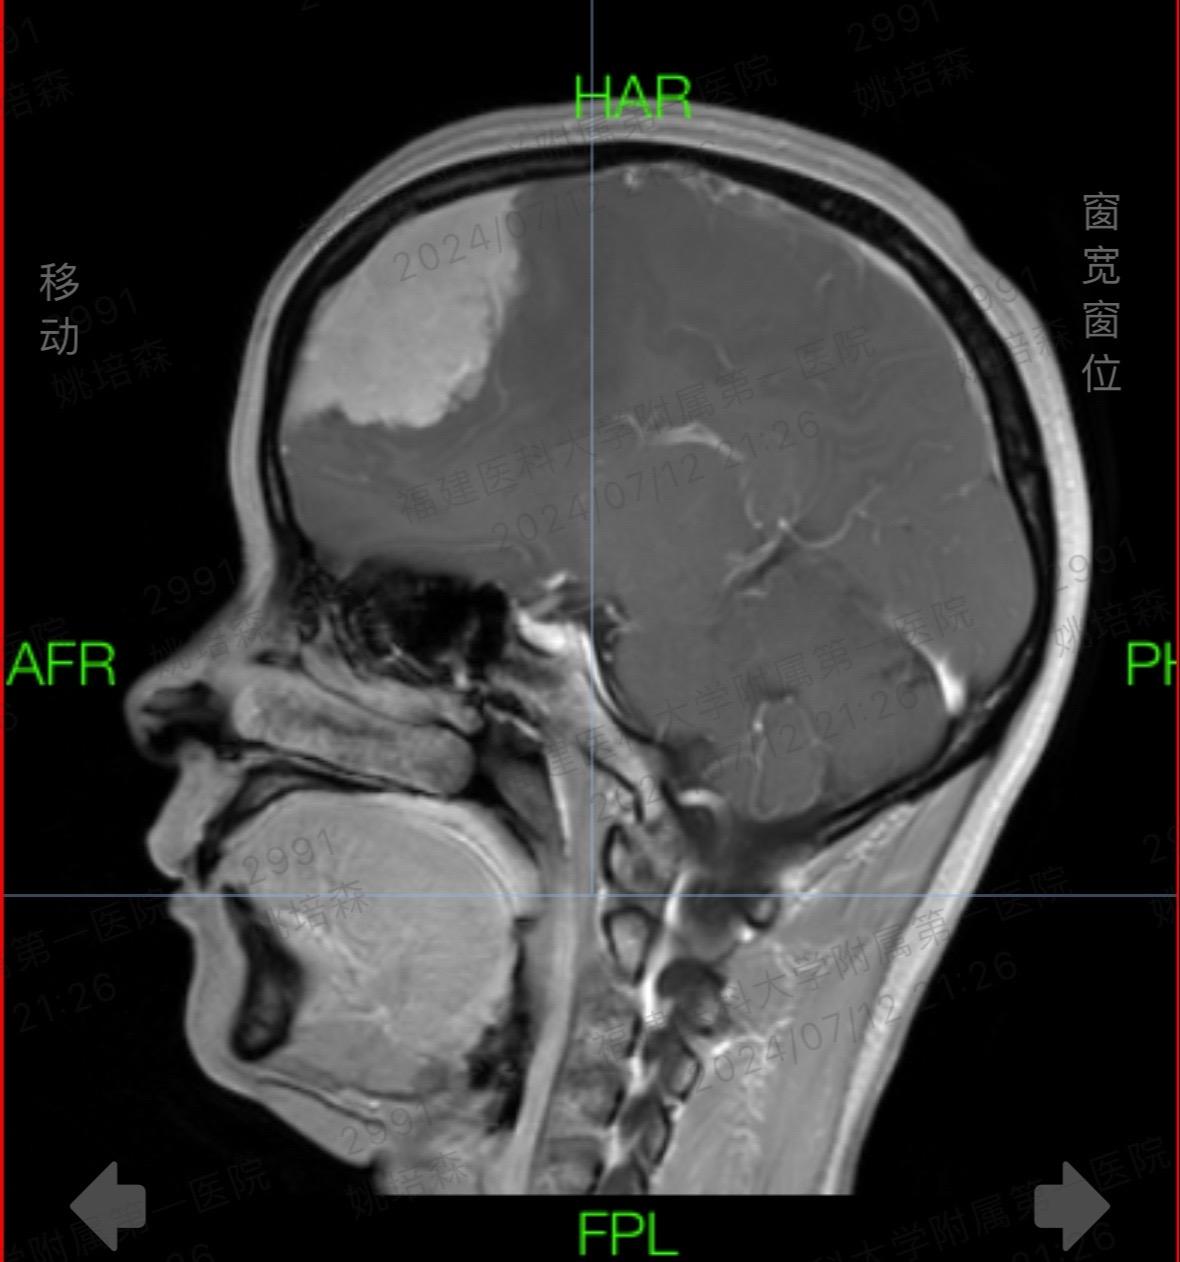

时光晃呀晃。连续10小时颅脑手术室日常 微创手术 手术,做了一台帕金森病,一台面肌痉挛,一台三叉神经痛,一台脑膜瘤,时光把我一整天晃走了,还让我累成了某某某!